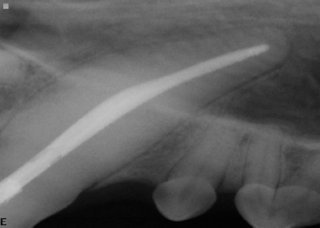

Upper fourth premolar tooth has three roots. Three endodontic files are used to clean out all these roots.

The roots are filled with an inert material.